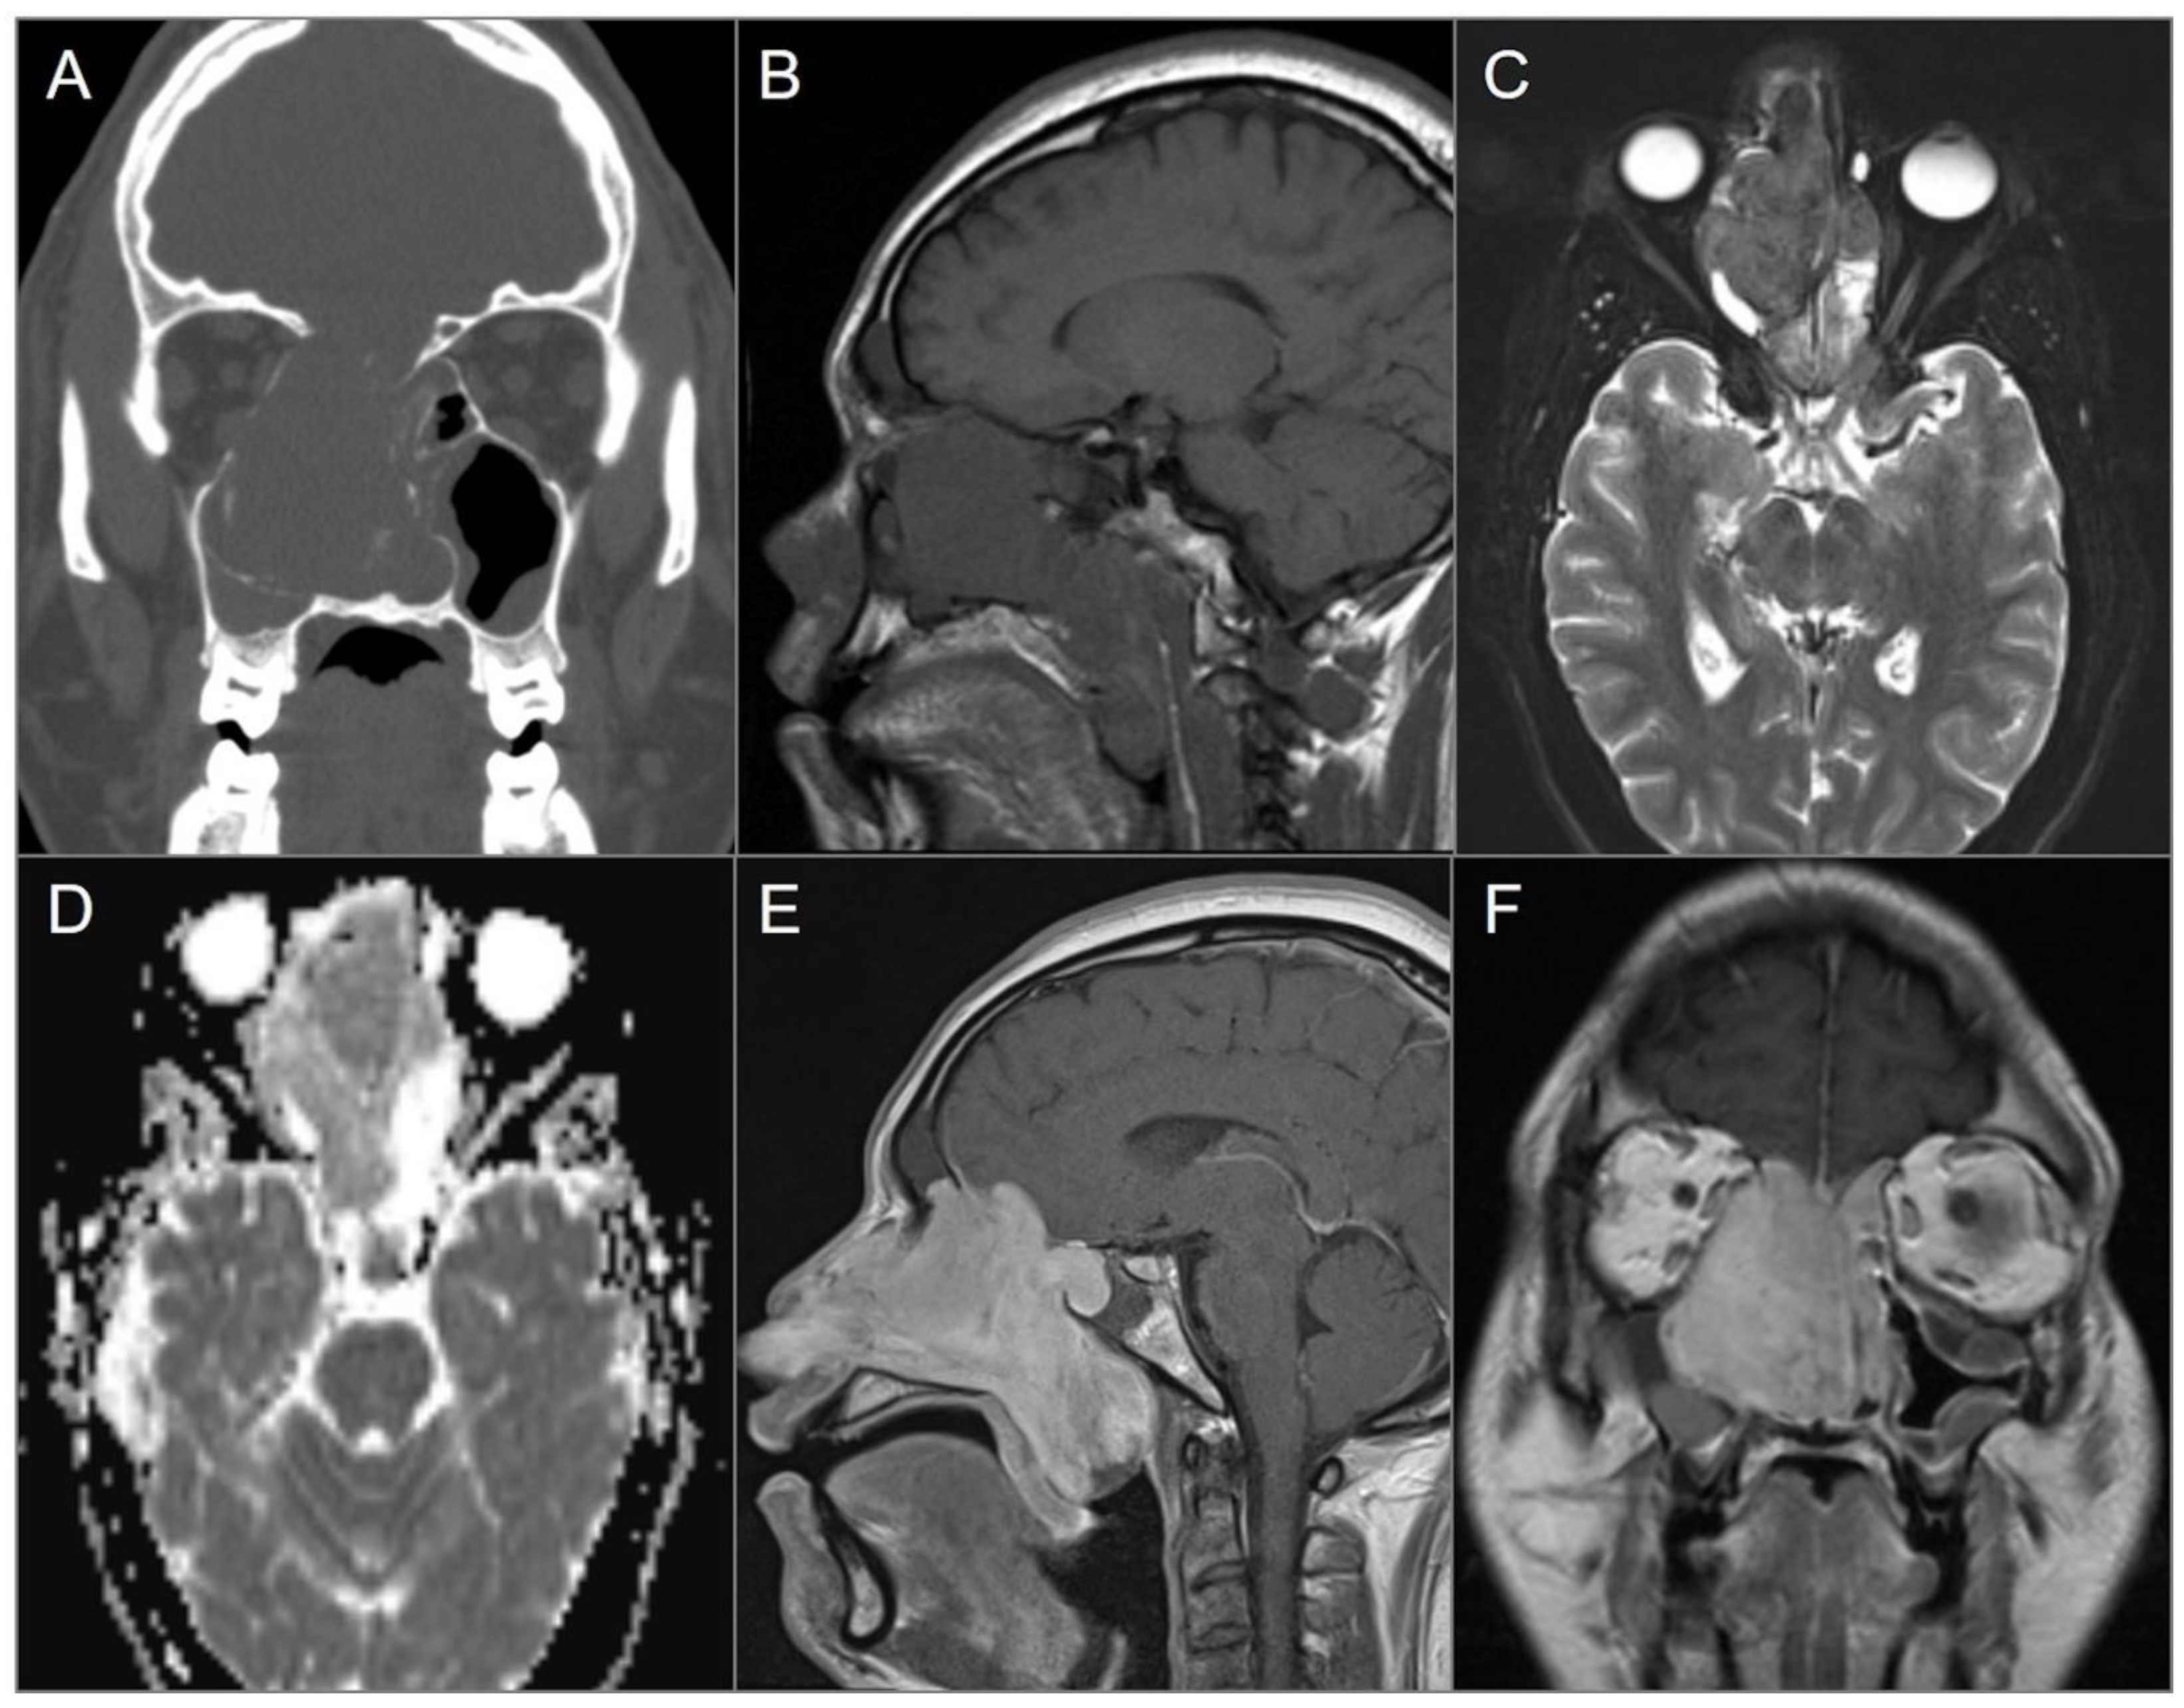

4.2.3. Olfactory Neuroblastoma